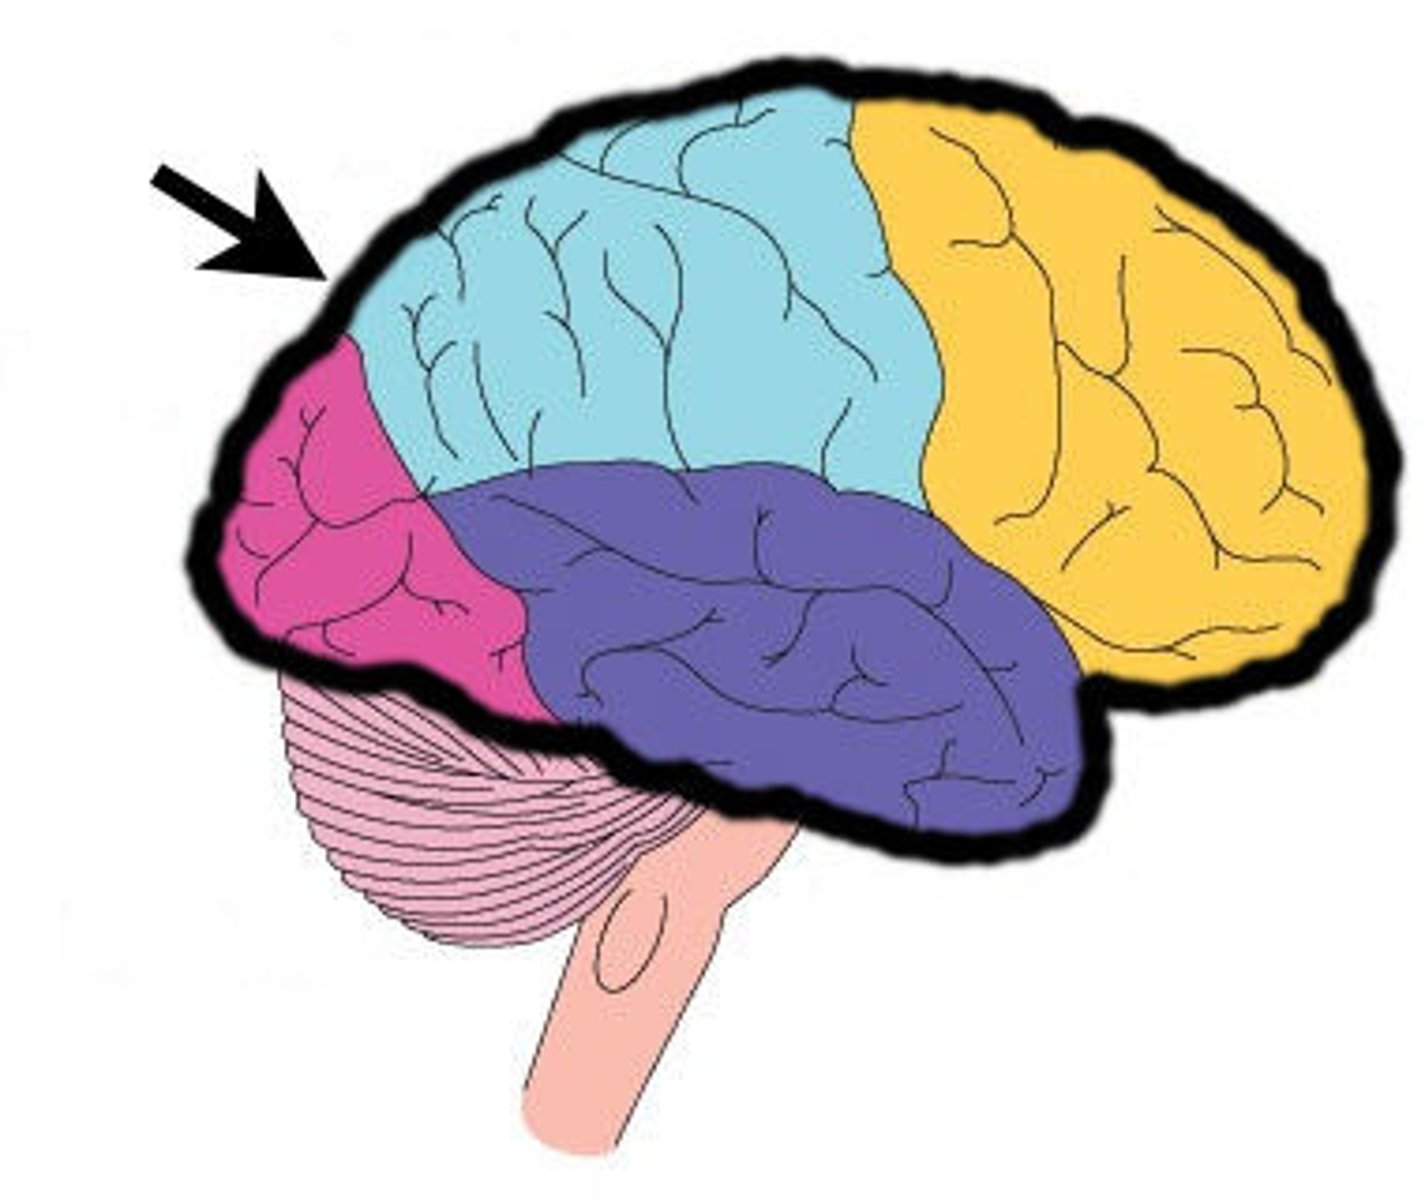

Lobes of the cerebrum

frontal, parietal, temporal, occipital

lateral cerebral sulcus

separates the frontal lobe from the temporal lobe

parieto-occipital sulcus

separates parietal and occipital lobes